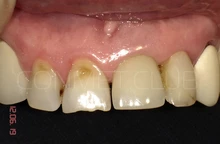

Контрольное фото через 6 недель после окончательного протезирования. Почти идеальная сохранность межзубных сосочков.

Итоговое фото через 6 недель после окончания протезирования.